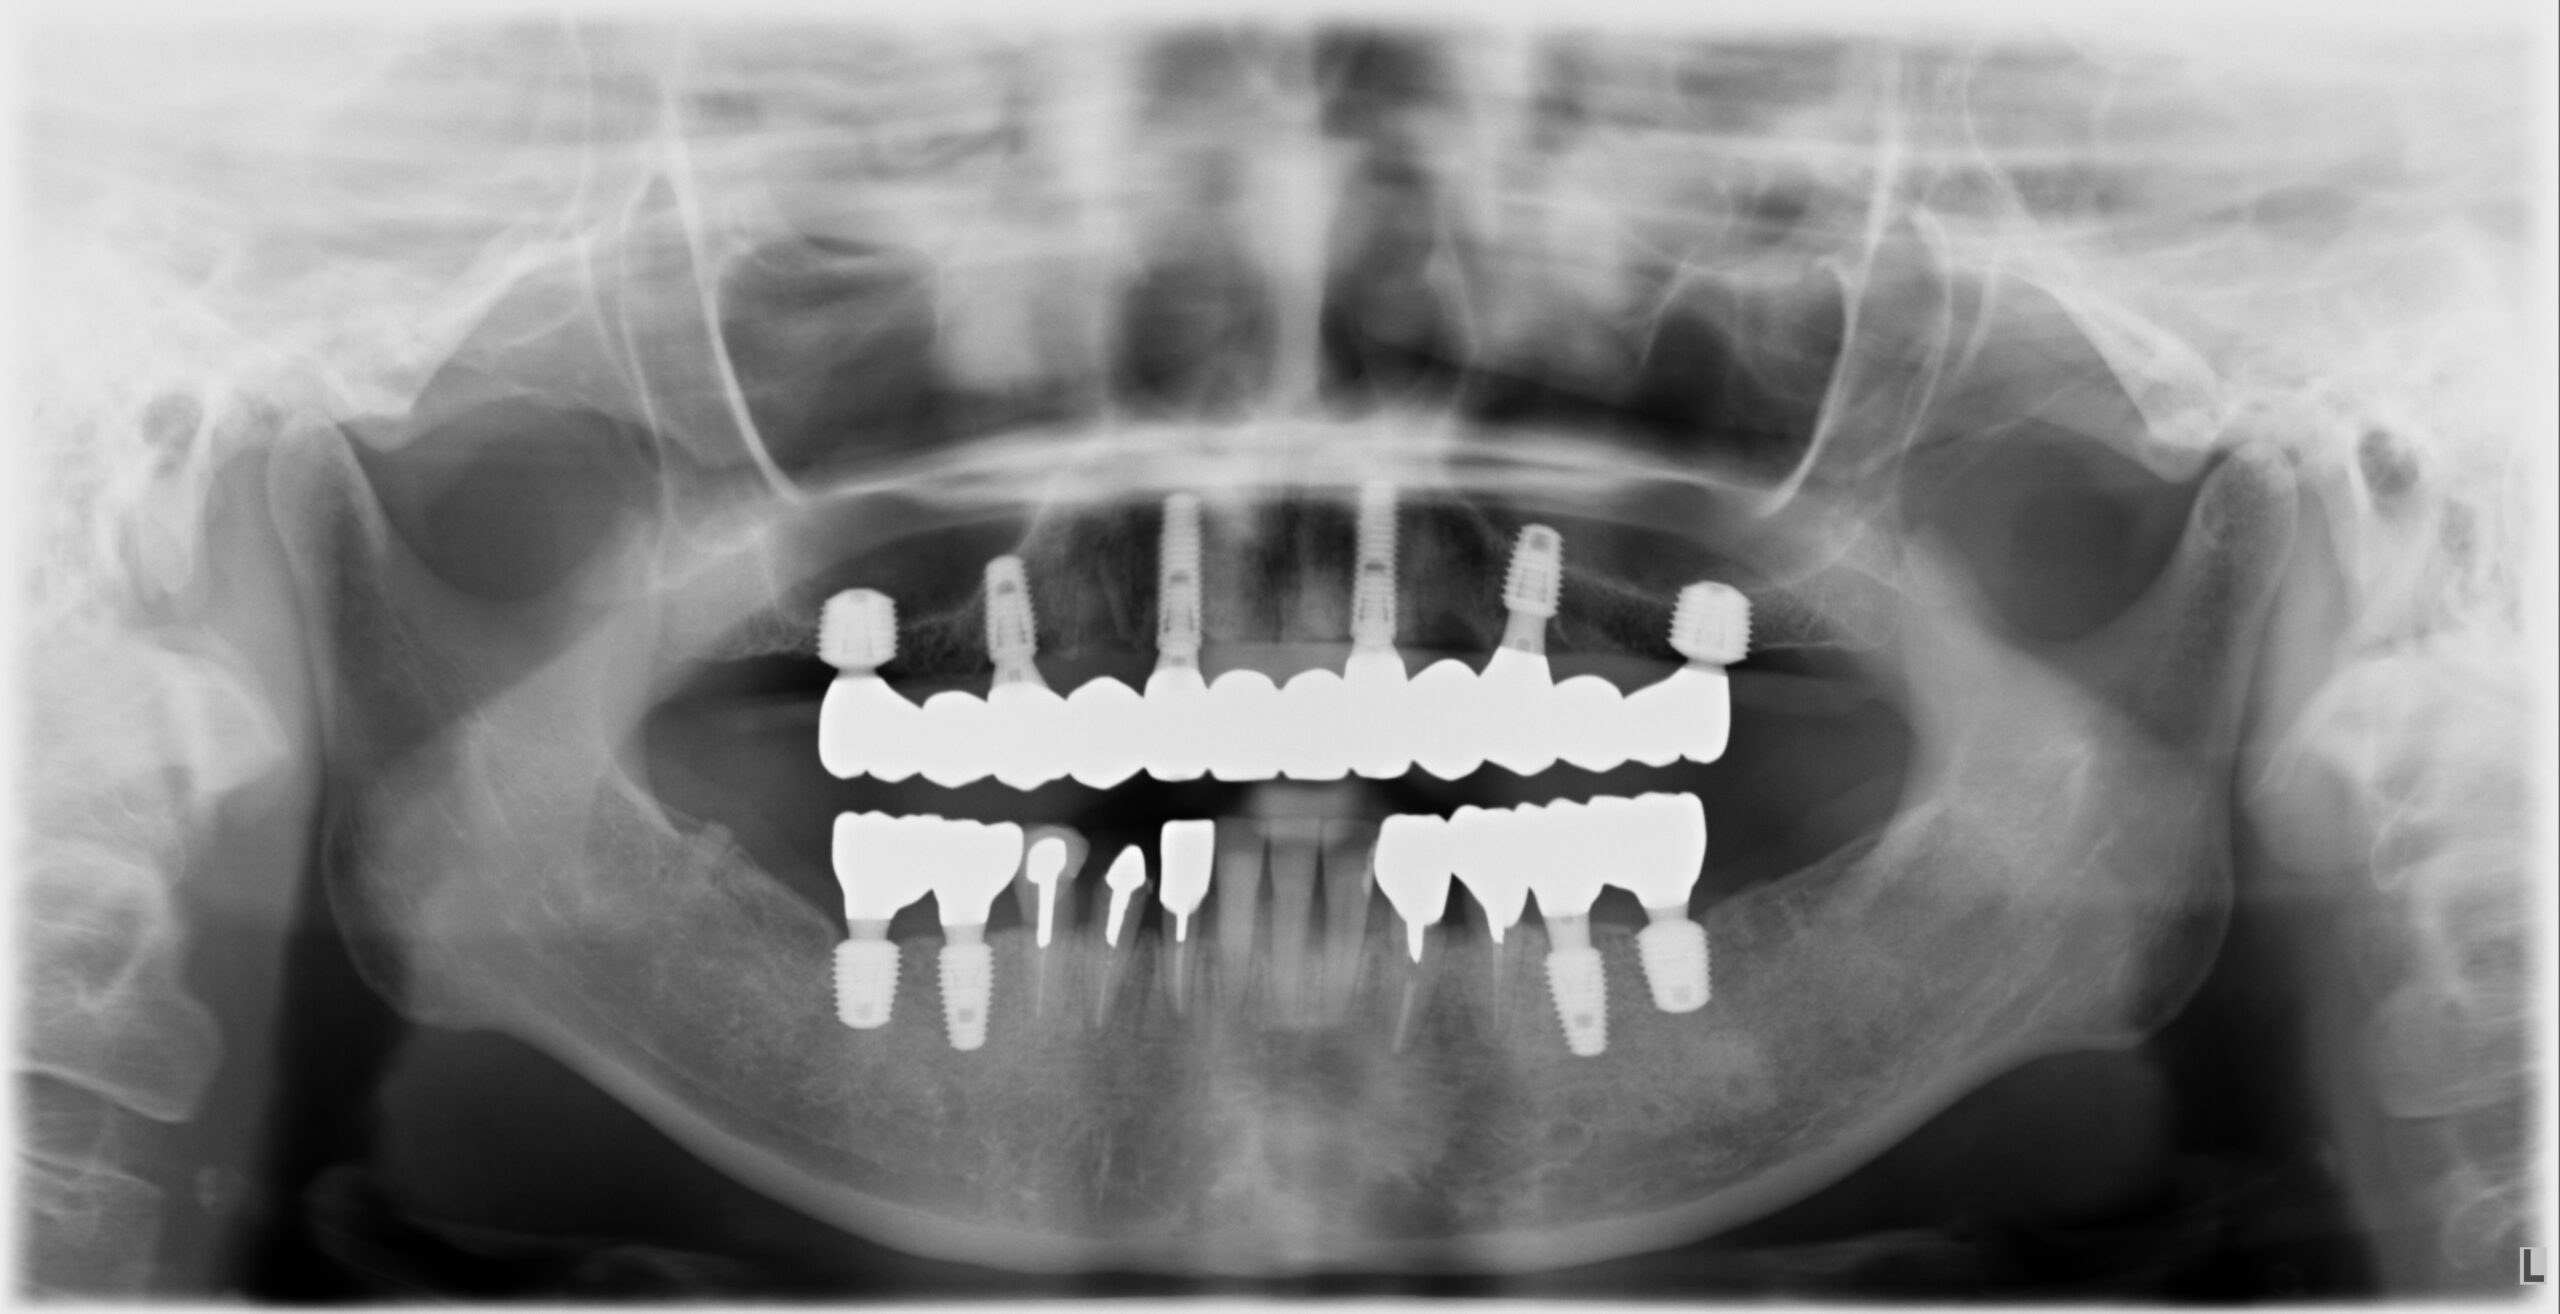

case.2

Before

After

| 概要 | 上顎の残存している歯は虫歯が深いので全て抜歯し、前歯は歯肉のラインが変化しないように歯根の外側を一部残してインプラントを埋入します。奥歯は上顎洞底まで距離がないのでソケットリフトをしてインプラントを埋入します。かみ合わせが低いことが原因で上 |

|---|---|

| 主訴 | 差し歯が外れているので治したい。奥歯で食事ができるようにしたい。上顎の前歯が出っ歯なので治したい。 |

| 治療期間 | 1年6ヵ月 |

| 治療回数 | 26回 |

| 治療費 | 400万円 |

| 治療内容 | 上顎に8本のインプラントを埋入してジルコニアブリッジで補綴 |

| 治療のリスク | 1次手術後は副鼻腔を刺激しないように、鼻をかんだりしないことが大切です。 |

※表示金額は全て税込です。